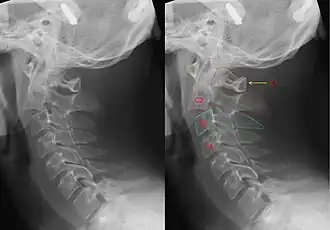

Röntgenfoto van de halswervelkolom met een hangman's fracture, hier ontstaan door een ongeval. Links zonder, rechts met annotatie. Duidelijk is te zien dat C2 (rode markering) naar voren is verschoven t.o.v. C3 (blauwe markering).

Dit type breuk wordt veroorzaakt door een plotselinge extreme overstrekking (hyperextensie) van de nek, eventueel ook gepaard gaande met een grote trekkracht langs de lengte-as van het lichaam. Door deze geweldsinwerking kan een breuk optreden in de axis (tweede halswervel). Daardoor kunnen nekwervels hun normale onderlinge samenhang verliezen en ten opzichte van elkaar gaan verschuiven, waarbij dan meestal de tweede nekwervel voorwaarts schuift ten opzichte van de derde. Daardoor kan het ruggenmerg ingeklemd of zelfs doorsneden worden: een hoog-cervicale dwarslaesie. Bij een dergelijk letsel treedt onmiddellijk een dodelijke verlamming op van het gehele lichaam inclusief de ademhalingsspieren, zodat het slachtoffer niet meer kan bewegen en dus ook niet ademen.